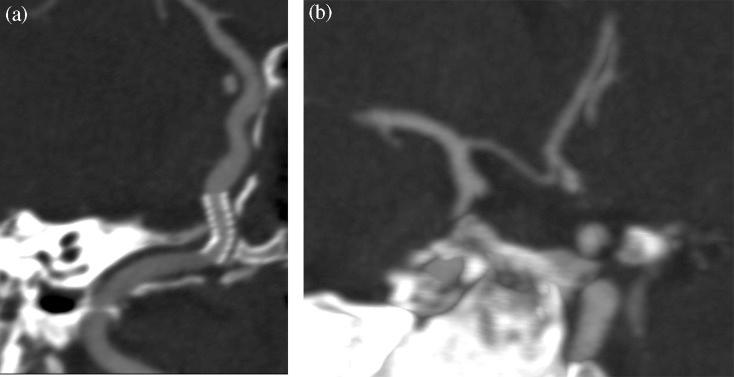

Acute endovascular repair of iatrogenic right internal carotid arterial laceration.

Carotid arterial bleeding is a feared and possible life-threatening complication of transsphenoidal surgery. We present a case of a meningioma that during resection had a serious complication with laceration of the internal carotid artery (ICA). These patients rarely undergo endovascular treatment, with indications mainly due to the development of pseudoaneurysms or penetrating trauma. However, endovascular treatment with covered stents of carotid arterial bleedings is a feasible alternative due to technical advances and smaller sized stentgrafts that expand treatment options.

颈动脉出血是经蝶窦手术令人恐惧且可能危及生命的并发症。我们报告一例脑膜瘤病例,该病例在切除过程中出现严重并发症,导致颈内动脉(ICA)撕裂。这些患者很少接受血管内治疗,其适应症主要是由于假性动脉瘤的形成或穿透性创伤。然而,由于技术进步以及尺寸更小的覆膜支架拓宽了治疗选择,采用覆膜支架对颈动脉出血进行血管内治疗是一种可行的替代方法。